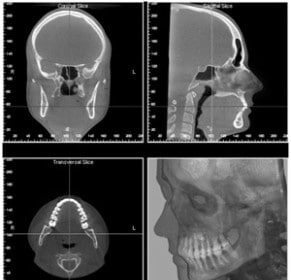

Le cabinet idéal pour une chirurgie Maxillo-Facial

Peu importe notre âge, nous avons toujours besoin de prendre soin et…